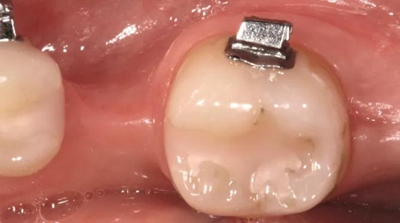

圖2a.病例1中,同期牙槽嵴增量和右下第一磨牙種植位點加速磨牙直立。術(shù)前臨床檢查顯示修復空間小、牙槽嵴吸收

圖2b.增量時,在受區(qū)和右下第二磨牙遠中進行牙槽嵴去皮質(zhì)術(shù)

圖5a. 病例2中右下第一磨牙加速種植位點改建。初期排齊期間

圖5b. 術(shù)前臨床檢查

圖5c. 翻全厚瓣后,看到嚴重的牙槽嵴吸收